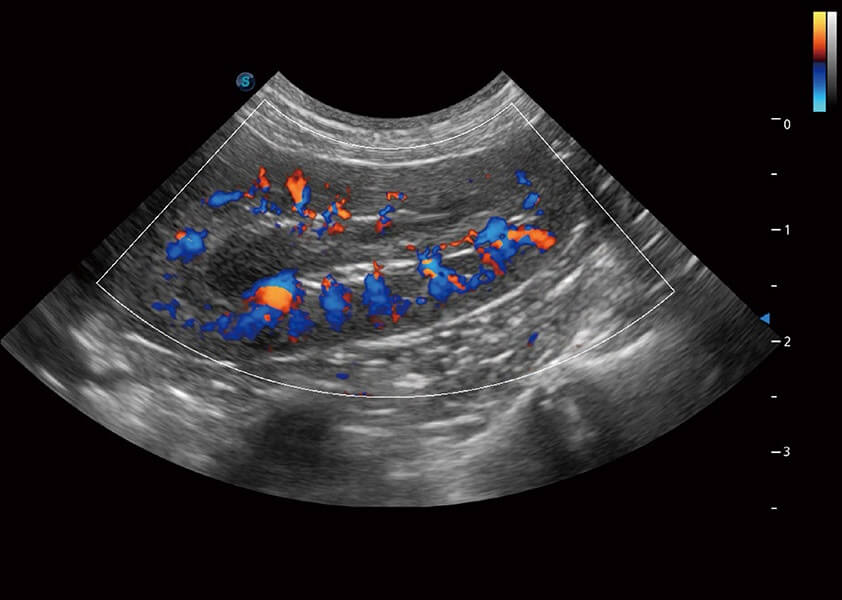

ProPet 60 作为一款高端台式动物超声设备,为动物医生的日常诊断提供了一系列贴合动物临床需求、解决临床实际问题的高级成像功能。凭借全系列高清探头,满足医生对腹部、心脏、生殖、浅表、肌骨等成像的所有需求,切实帮助您提升检查效率,提高诊断信心。

动物是人类最亲密的朋友和最值得信赖的伙伴。竞技宝(JJB)官方网站也一直致力于探索动物专用的超声影像解决方案。 全新推出的ProPet系列,是竞技宝(JJB)官方网站在动物超声影像智能化、专业化、精准化的一次跨越式革新。动物不能用言语来表述自己的不适,通过超声影像,ProPet系列搭建了动物医生与不同物种沟通的“桥梁”,为动物医生注入了“治愈之力”。